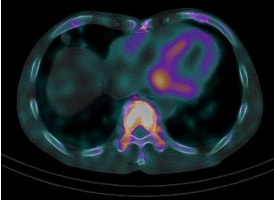

サルコイドーシスは、非乾酪性肉芽腫という病理変化を伴う炎症性疾患です。心臓以外にも眼、皮膚、肺やリンパ節に起こり得ます。心臓においては、心筋の収縮障害から進行すれば心拡大が起きます。不整脈を併発しやすいことも知られています。診断には心臓MRIや血液検査のほかに、心臓にブドウ糖が取り込まれているか調べる核医学検査であるFluorodeoxyglucose-Positron Emission Tomography(FDG-PET)が病勢の把握に有用です。

心サルコイドーシスの活動期

心サルコイドーシスの活動期

ステロイド治療により

ステロイド治療により炎症・免疫反応が軽減